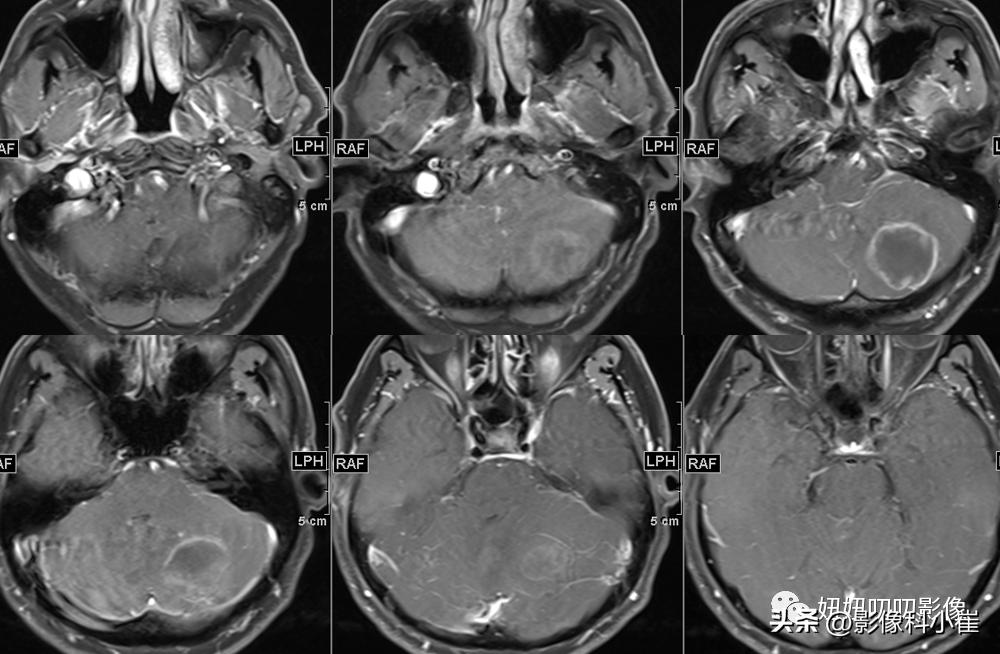

左侧小脑半球片状长短T1等长T2 异常信号,边界不清,大小约3.2X2.9X2.4cm,T2-Flair呈等高信号,周围见斑片状水肿带,DWI 示病变明显弥散受限,增强扫描可见不均匀环状强化。双侧放射冠、皮层下另见少许斑点状等长 T1、长T2 异常信号灶,T2 Flair 呈高信号,DWI未见明显弥散受限,增强扫描未见明显异常强化。第四脑室受压变窄,幕上脑室系统未见明显扩张。脑沟、脑裂略增宽。中线结构无移位。双侧筛窦、上领窦粘膜增厚。

这个病有意思,周边T2黑黑的,弥散受限这么明显,强化还是环形强化,从环形强化入手?转移,胶质母,脓肿。从弥散收入,淋巴瘤,脓肿,胶质母,T1还有出血,信号不均匀,边界清楚。其实看到出血觉得是胶质母,其实看看弥散的均匀度,和环状强化的边,并不是那么花环样子,加上白细胞高,可能还是脓肿。

病理是脓肿;

慢慢对比,看下边界,看下DWI的样子,自己慢慢品!!!